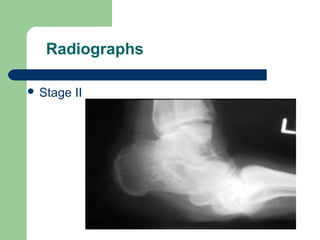

Radiographs

 Stage II

Radiographic Staging

(Eichenholtz, 1966)

 I Developmental (acute) stage

 II Coalescence (quiescent) stage

 III Consolidation (resolution) stage

Radiographic Staging (Eichenholtz, 1966) I Developmental (acute) stage  II Coalescence (quiescent) stage  III Consolidation (resolution) stage